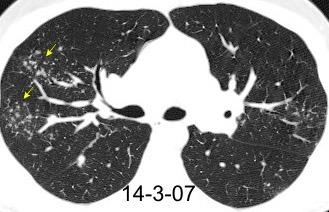

PATRÓN DEL “ÁRBOL EN BROTES”

Bronquiolos terminales rellenos de pus, caseum, líquido o células

Walker CM et al. Imaging Pulmonary Infection: Classic Signs and Patterns. AJR. 2014

Agudas

Bronconeumonía

Bronquiolitis infecciosa

Crónicas

Tuberculosis

Bronquiolitis folicular y infecciosa

Aspiración Panbronquiolitis difusa

Adenocarcinoma.

“Embolismo tumoral”

TB. probada. Adenocarcinoma gástrico

(Tree in bud)

Panbronquilitis difusa

Aspiración

Tb. Endobronquial Micobacteria atípica

Bronquiectasias

Fibrosis quística

Ca bronquioalveolar

Metástasis intravascular